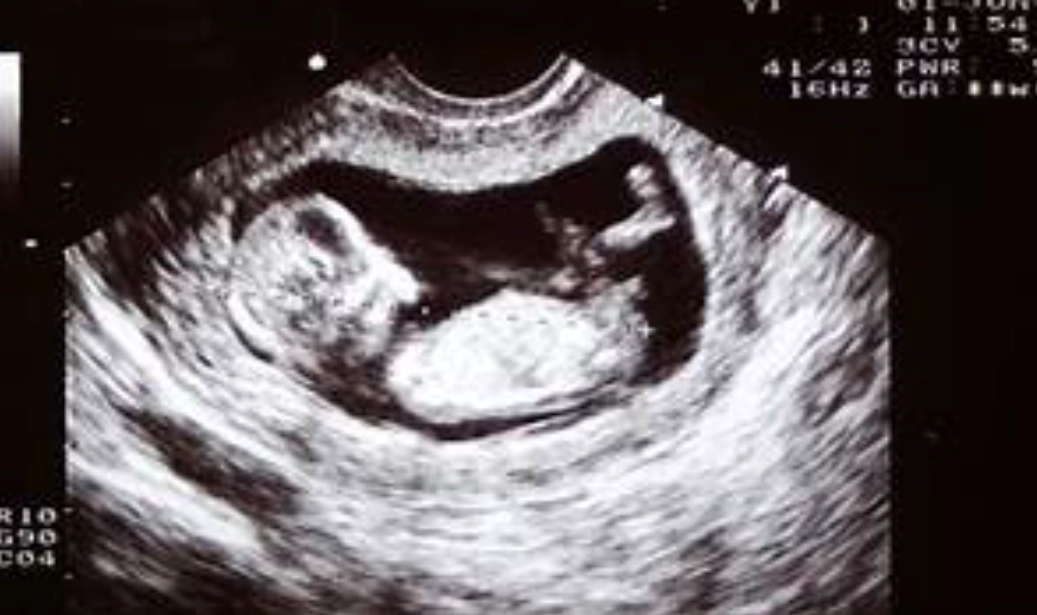

The Ultrasound: Seeing is Believing

This is the gold standard for first-trimester reassurance. There are typically two key scans:

| Scan Timing | What They're Looking For | Why It's Reassuring |

|---|---|---|

| 6-8 Weeks (Dating Scan) | Gestational sac, yolk sac, fetal pole, and most importantly—a fetal heartbeat. | Confirms the pregnancy is in the uterus (rules out ectopic). A detectable heartbeat after 7 weeks drastically reduces miscarriage risk. |

| 11-13 Weeks (NT Scan) | Nuchal translucency measurement (fluid at back of baby's neck), nasal bone, basic anatomy. | Combined with blood work, this screens for chromosomal abnormalities like Down syndrome. It also provides a detailed check on early development. |

One insider tip: before 7 weeks, it's common not to see a heartbeat yet. Going in too early can cause unnecessary anxiety. Waiting for that 7-8 week window often provides clearer, more reassuring results.